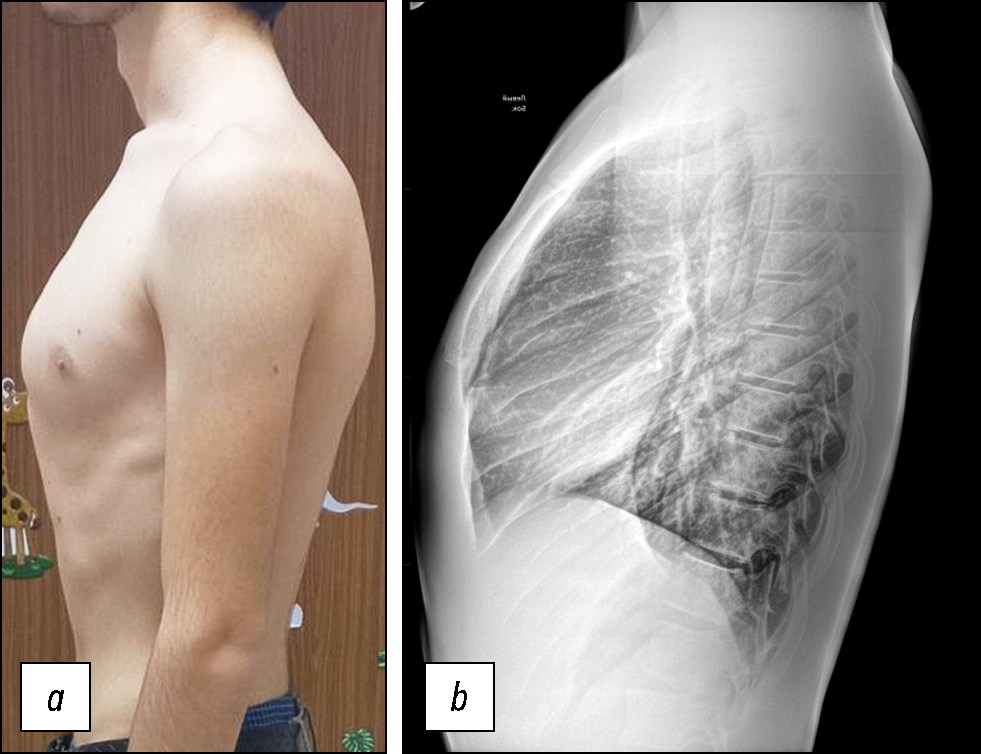

На рис. 1 представлены результаты ортопедического осмотра и рентгенограмма грудного отдела позвоночника ребёнка 16 лет с КДГК и жалобами на боль в нижнегрудном и поясничном отделах позвоночника.

Рис. 1. Результаты клинического и инструментального обследования юноши 16 лет с килевидной деформацией грудной клетки: a — привычная поза ребёнка — ослабленная осанка, крыловидное выстояние лопаток, приведение кпереди плеч, шейный гиперлордоз; b — приведение переднего отдела левой стопы; c — стрии на спине в поясничной области; d — на рентгенограммах грудной клетки в боковой проекции — склероз и узурация концевых пластинок позвонков (признаки ювенильной остеохондропатии).

Fig. 1. The results of a clinical and instrumental examination of a 16-year-old boy with pectus carinatum: a — the child’s usual posture — weak posture, pterygoid scapular protrusion, adduction of the shoulders anteriorly, cervical hyperlordosis; b — adduction of the left forefoot; c — stretch marks on the back in the lumbar region; d — sclerosis and usuration of the end plates of the vertebrae (signs of juvenile osteochondrosis) on the lateral radiographs of the chest.